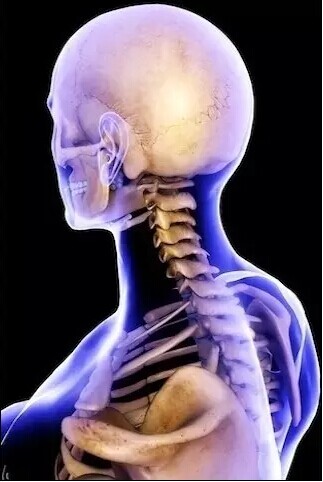

头颅、颈椎

头颅

颈椎、大脑